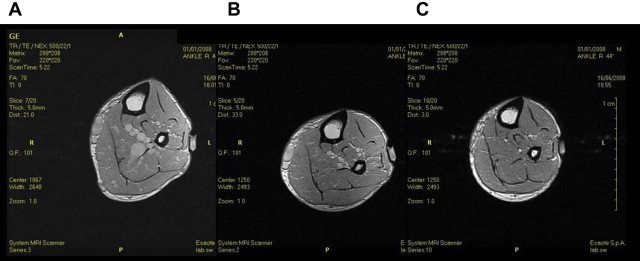

To narrow or occlude the venous system, the compression pressure must be higher than the intravenous pressure. This depends on the body position because venous pressure varies in different body positions. It has been shown that it is possible to narrow or occlude the veins with an external pressure of 20 mm Hg in the supine position, 50 mm Hg in the sitting position, and 70 mm Hg in the standing position. It was also demonstrated that in the sitting position a pressure of 40 mm Hg was enough to narrow (but not occlude) the calf veins; but when the patient was asked to do foot dorsiflexions with an inelastic cuff, the pressure increased to 60 mm Hg, resulting in vein occlusion. These data were confirmed by magnetic resonance imaging studies, which showed that in the standing position, a pressure of 40 mm Hg was not able to occlude the veins, that were only completely occluded with a pressure of 80 mm Hg ( Fig. 2 ).